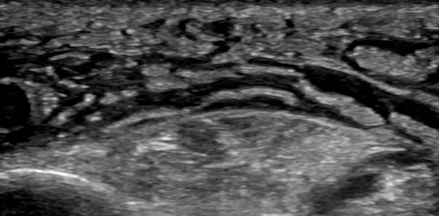

Point-of-care ultrasound can visualize the purulent collection of an abscess. Point-of-care ultrasound reduces failure-to-diagnose rate and decreases the number of inappropriate incision and drainage procedures of cellulitis.20 Cellulitis on ultrasound shows scattered fluid pockets in a cobblestoning pattern (see Figure 2), whereas an abscess will show a distinct fluid collection.21 (See Figure 3.)

Figure 2. Ultrasound of Cellulitis |

![]() |

Source: Image used with permission from Andrea Kaelin, MD. |